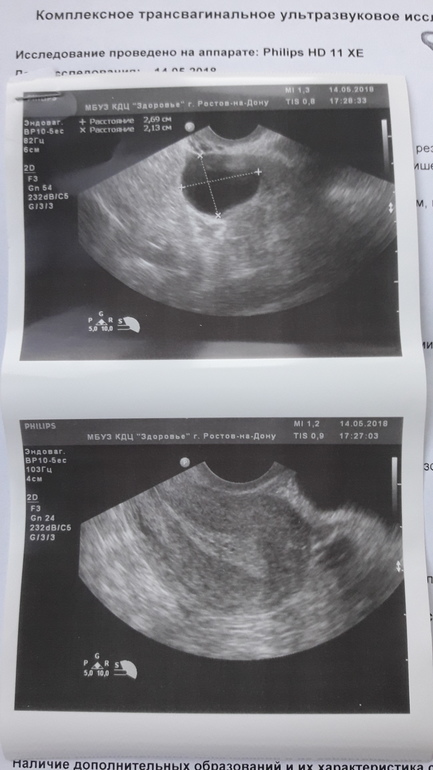

ФолликулометрияДобрый день девочки! 19.04.18 была лапара по поводу СПКЯ . Сегодня 14.05.18 решила пойти на узи сама, т.к. мерию БТ и по ней должна была быть овуляция (по графику по крайней мере) 7.05.18

По узи совсем ничего не поняла, а врач даже объяснять не стала(((

Вам лапару без гистеры делали? Если было спкя, то соотв и гормоны плясали как хотели, то и с эндиком могут быть проблемы. На узи похоже на фоллик кисту, дождитесь след М и просите укол хгч, что бы лопнул, после операции надо быстро Б, пока эффект держится

меня лично настораживает эндометрий неоднородный и не пишет за доминантный фолликул. нет его, нет овуляции. у вас после операции прошли дни веселые? день операции считается новым циклом.

Нет, еще не прошли, жду их. Надеялась, что эндометрий будет нормальный, но он как всегда очень маленький. Вообще больше его хотела посмотреть.

Понять не могу, что за включение в левом яичнике 29×21 мм...